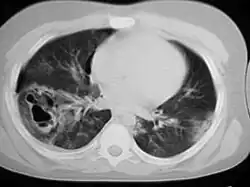

| A CT scan showing a pulmonary contusion (red arrow) accompanied by a rib fracture (purple arrow) | |

Computed tomography

Computed tomography (CT scanning) is a more sensitive test for pulmonary contusion,[8][38] and it can identify abdominal, chest, or other injuries that accompany the contusion.[43] In one study, chest X-ray detected pulmonary contusions in 16.3% of people with serious blunt trauma, while CT detected them in 31.2% of the same people.[50] Unlike X-ray, CT scanning can detect the contusion almost immediately after the injury.[48] However, in both X-ray and CT a contusion may become more visible over the first 24–48 hours after trauma as bleeding and edema into lung tissues progress.[51] CT scanning also helps determine the size of a contusion, which is useful in determining whether a patient needs mechanical ventilation; a larger volume of contused lung on CT scan is associated with an increased likelihood that ventilation will be needed.[48] CT scans also help differentiate between contusion and pulmonary hematoma, which may be difficult to tell apart otherwise.[52] However, pulmonary contusions that are visible on CT but not chest X-ray are usually not severe enough to affect outcome or treatment.[42]